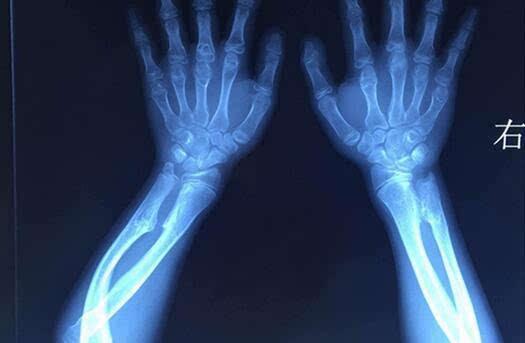

骨软骨瘤是最常见的良性骨肿瘤。其病因至今尚未明确。常见于长骨的干骺端,也可发生在肩胛骨、骨盆和脊柱附件上。肿块为位于骨表面的骨性突起物,表面有软骨帽,中间有髓腔。骨软骨瘤好发于10—20岁的青少年,,占良性骨肿瘤的1/3。大小随着人体的发育而逐渐增大,18岁后肿瘤通常会停止生长。

临床上有单发性和多发性之分。单发性骨软骨瘤恶变率低,约1%。多发性骨软骨瘤在医学上多称为遗传性多发骨软骨瘤。遗传性多发骨软骨瘤有家族遗传性,较单发性骨软骨瘤恶变率高,据报道其恶变率在5%到25%之间。

男性多发,肿瘤分布广泛且相对对称。在全身任何存在软骨的骨骼中几乎都有可能发生。由于肿瘤多发,所以很难依据外科手段全部切除。多表现为全身多发的骨性包块,常伴有骨骼短缩和畸形,如膝、踝、肘、腕关节的内外翻畸形。影像学上和单发的骨软骨瘤基本相同,只是肿瘤数量上的不同及存在骨骼畸形而已。